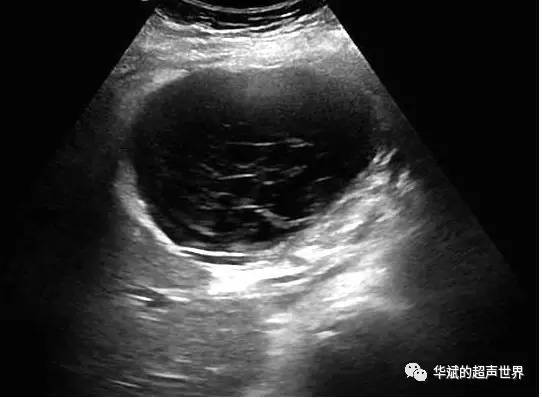

肝囊肿的诊断主要依靠影像学检查。在肝囊肿的定性方面,一般认为超声波检查比CT更准确。B超对肝囊肿的检出率可达98%。但在全面了解囊肿的大小、数目、位置,及其与周围脏器关系方面,CT检查的指导作用明显优于B超。通常,肝囊肿并不导致肝功能异常,也不会发展为肝癌。但有时为了鉴别诊断,某些血液检查仍然是必要的,如血液甲胎蛋白(AFP)检查,可以帮助排除原发性肝癌。

大多数肝囊肿体积很小,直径仅1~2cm,似葡萄大小,有些囊肿可以长得很大,直径可达10~20cm。肝囊肿可单发,也可以多发(在肝内散在分布)。大多数肝囊肿不会长大。一般情况下,肝囊肿不破裂、不出血、不感染,也不恶变。仅少数患者可能会发生囊内出血,致使囊液呈血性或伴血块,有时可继发感染。